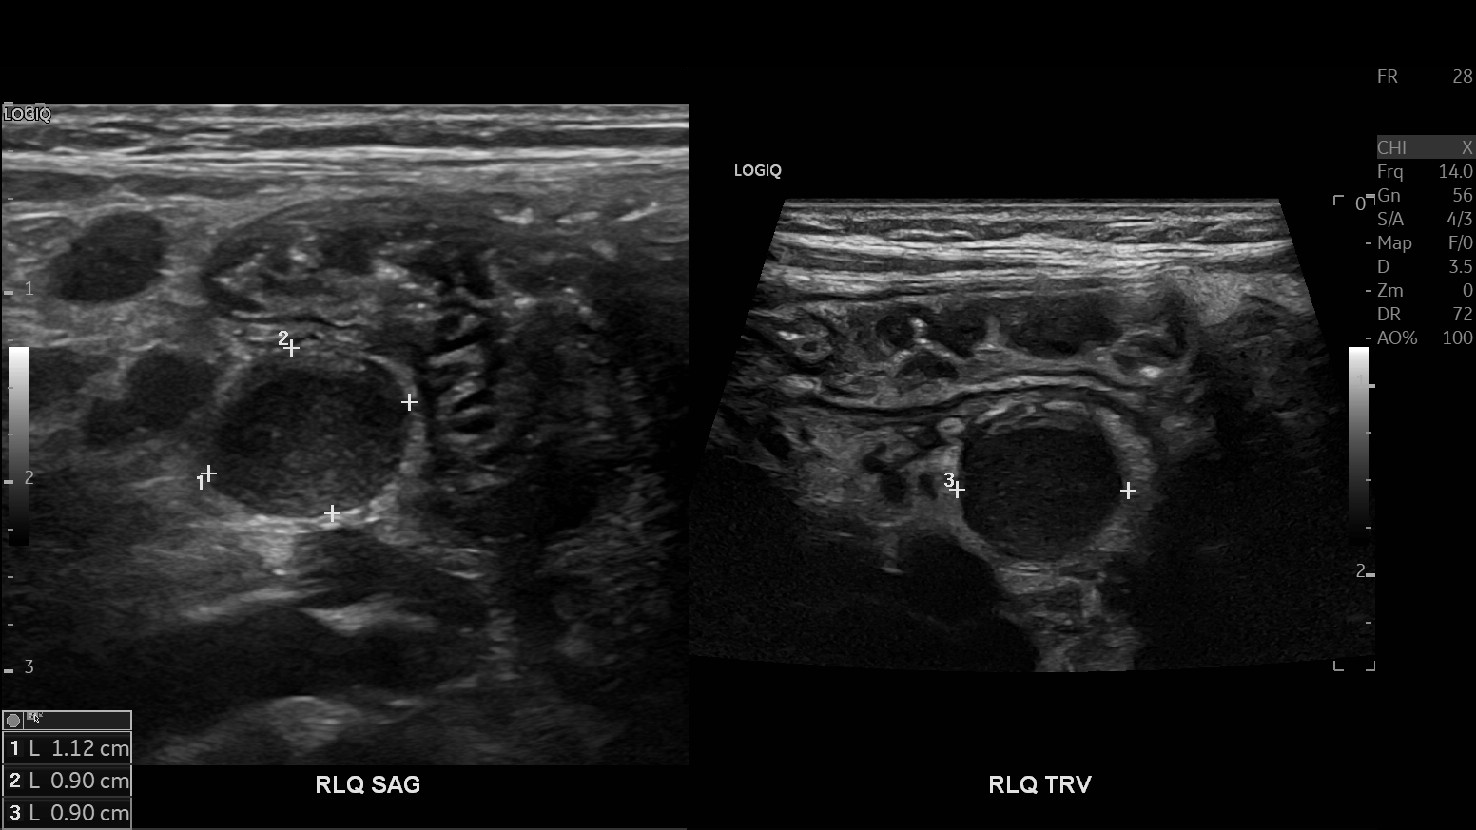

Appendicitis 12

0.9 cm positive appendicitis, with peripheral free fluid, and fat stranding.